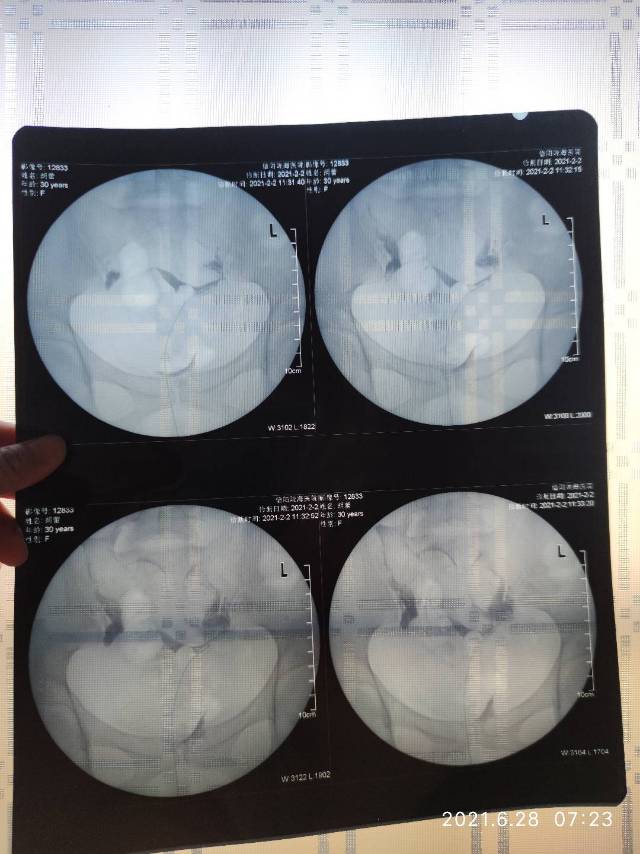

我今年30岁,备孕大概有五年了,一直没怀上,2019年西医促排一年,卵泡也有优势卵泡,没怀上,后来九月份做了输卵管造影以及通水,显示输卵管通而不畅,术后促排两个月还是没怀上。后来就没管了,在家休息。2020年由于月经推迟不来,五月份看了中医,吃药调理月经以及中医促排6个月,优势卵泡有,排卵后黄体不生,由于促排太多,又在家调养。今年2月份在信阳陇海不孕不育医院,去检查,查的说输卵管上举加粘连,宫颈有糜烂,医生建议做腹腔镜手术,后来由于开工,就来广州上班,没有做成,月经一直推迟,就去广州中医药来了调理月经的药,吃了大概半个月,月经来了,然后医生建议直接做试管。这个比较省事。目前月经不规律,推迟。